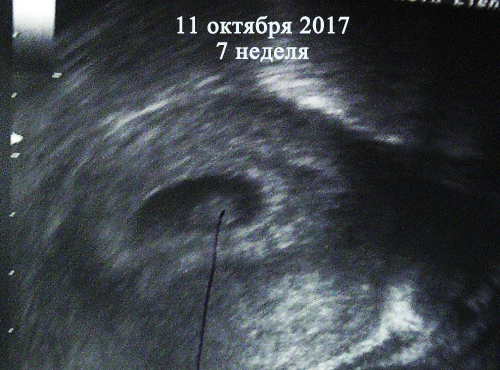

была в 5 недель с чем-то, не было эмбриона еще, вот узи за 6,4 недель

вот картинка

02.09.2020